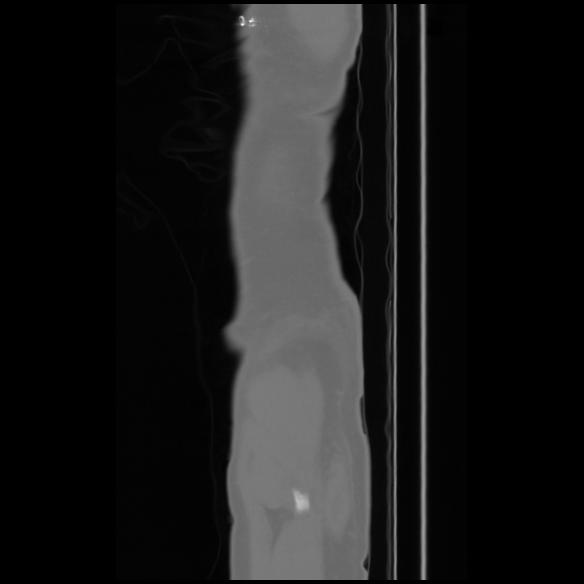

7 CUERPO,CE,Sagittal,3.000,CUERPO,Sagittal,